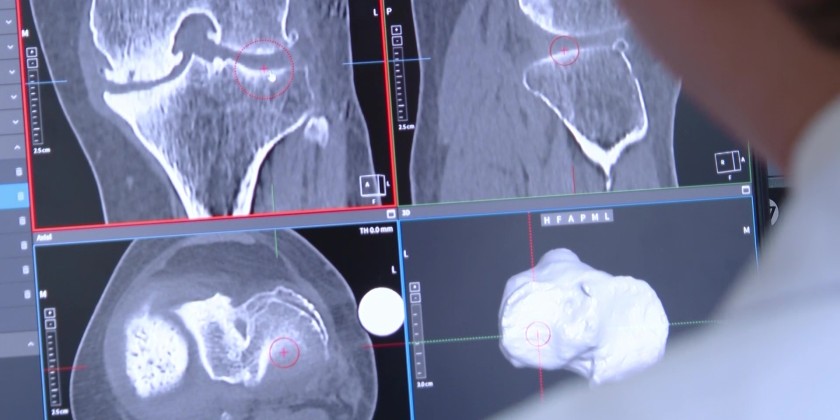

In Viet Nam, AI-powered surgical robot for surgery was already approved for patients’ knee and hip replacements. It marked a significant milestone for this patient who admitted at a hospital in Ho Chi Minh City after more than a decade of limited mobility.

She was also among the first patients in Viet Nam to undergo surgery using the CUVIS-Joint robotic system. The AI-assisted technology enables highly precise bone cutting, which helps minimize surgical impact and reduce damage to surrounding tissue, leading to faster recovery. Despite using advanced systems for joint replacement globally, the procedure costs around one-tenth of similar surgeries overseas in Viet Nam.